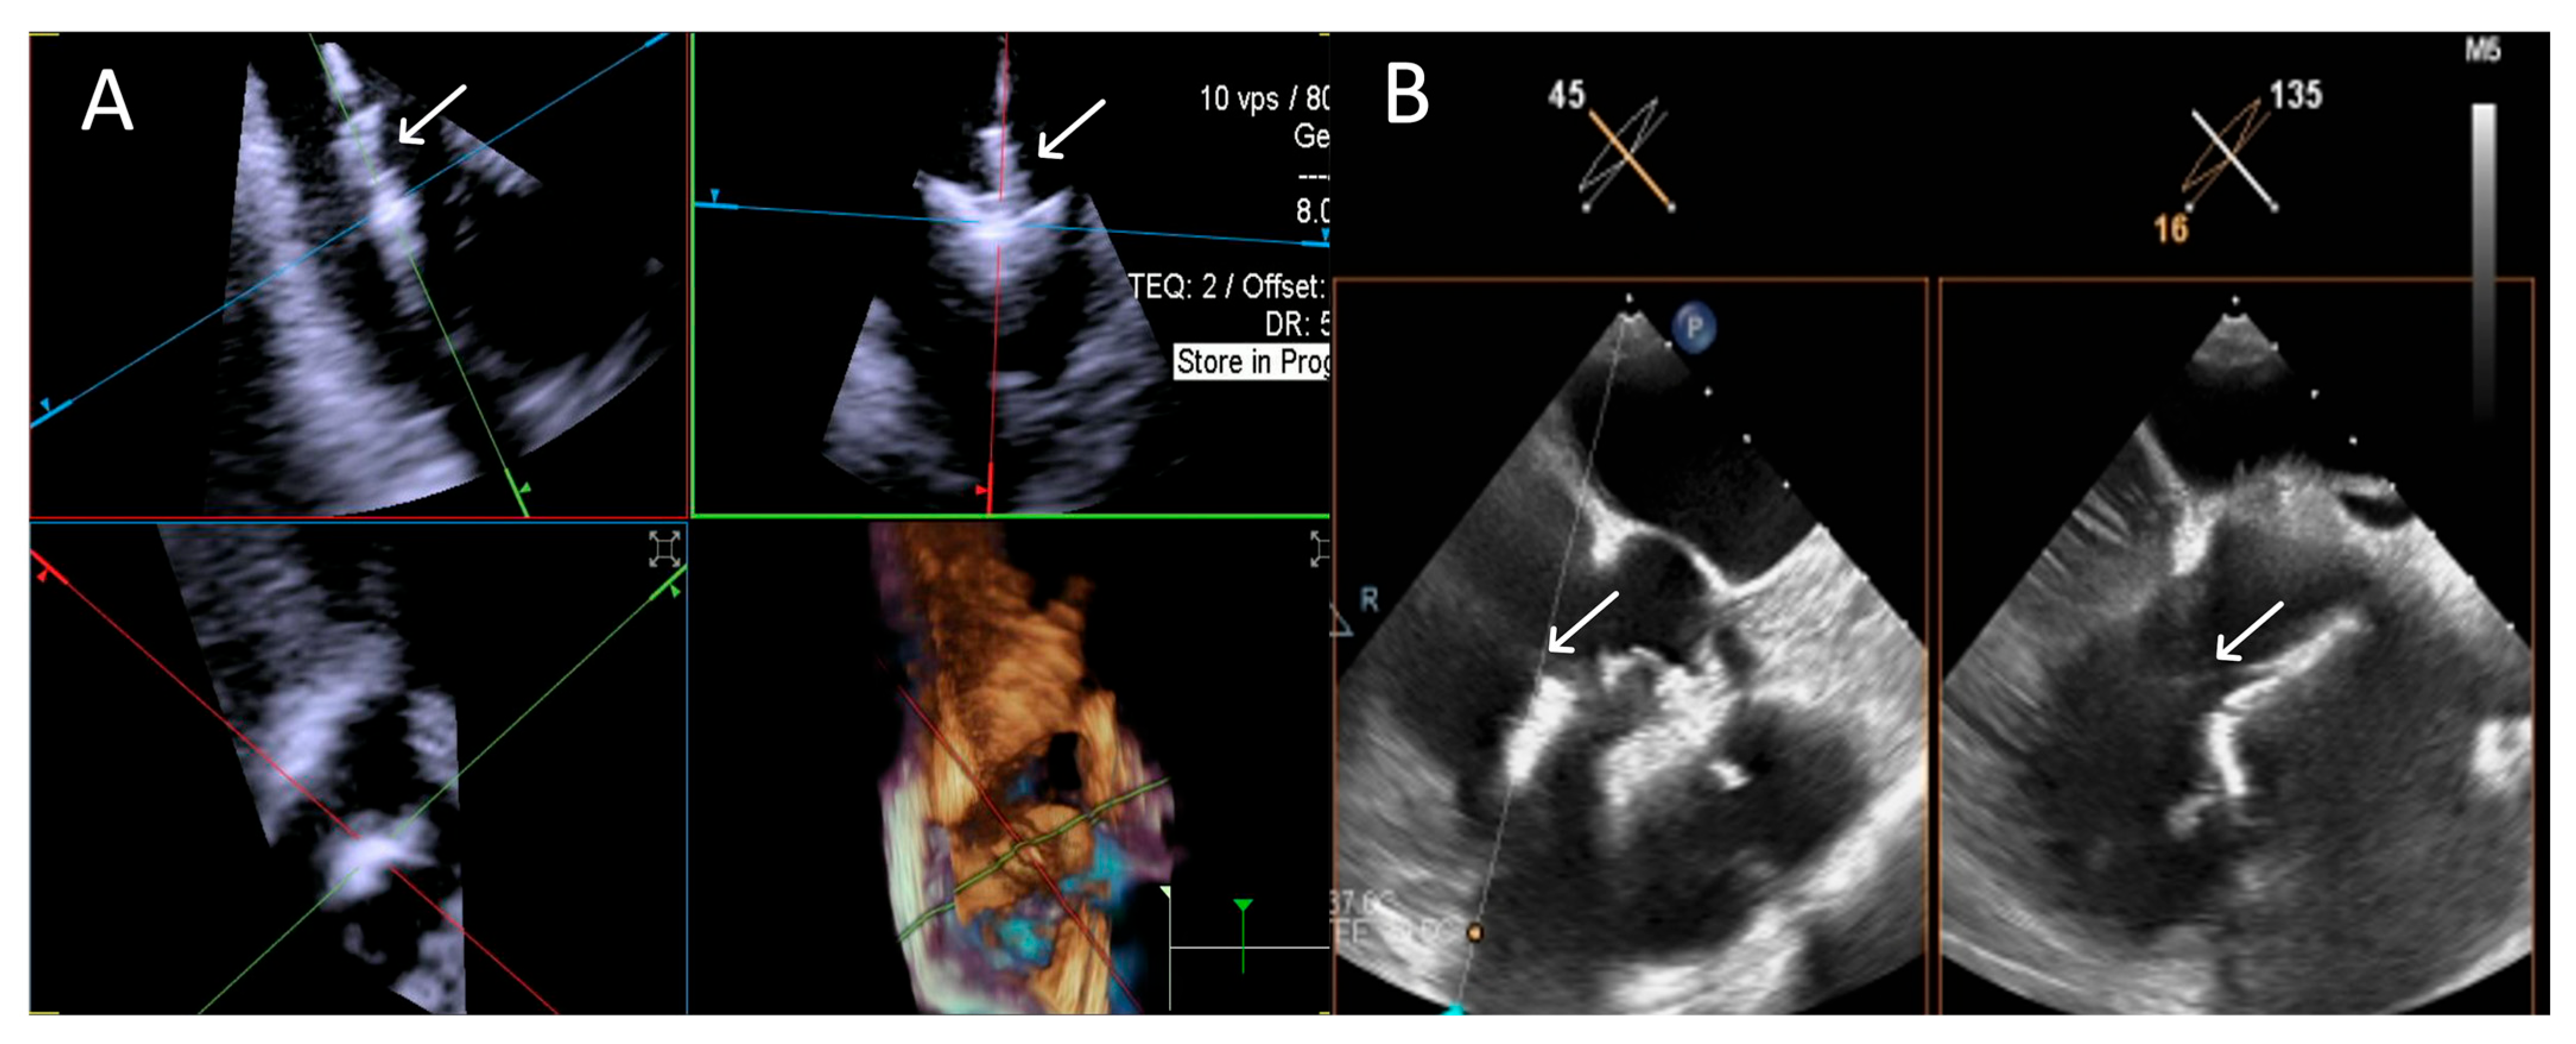

- Step number 1: assessment of tricuspid valve anatomy.

- Step number 2: identification of the target lesion.